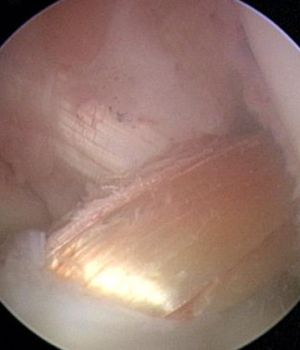

Die Operation findet sowohl für die Naht als auch für den Ersatz minimalinvasiv in Schlüssellochtechnik und rein arthroskopisch statt.

Nach einer arthroskopischen Inspektion des Gelenkes und der möglichen Reparatur von Begleitverletzungen wird sowohl im Oberschenkel als auch im Unterschenkel ein Kanal im Knochen angelegt.